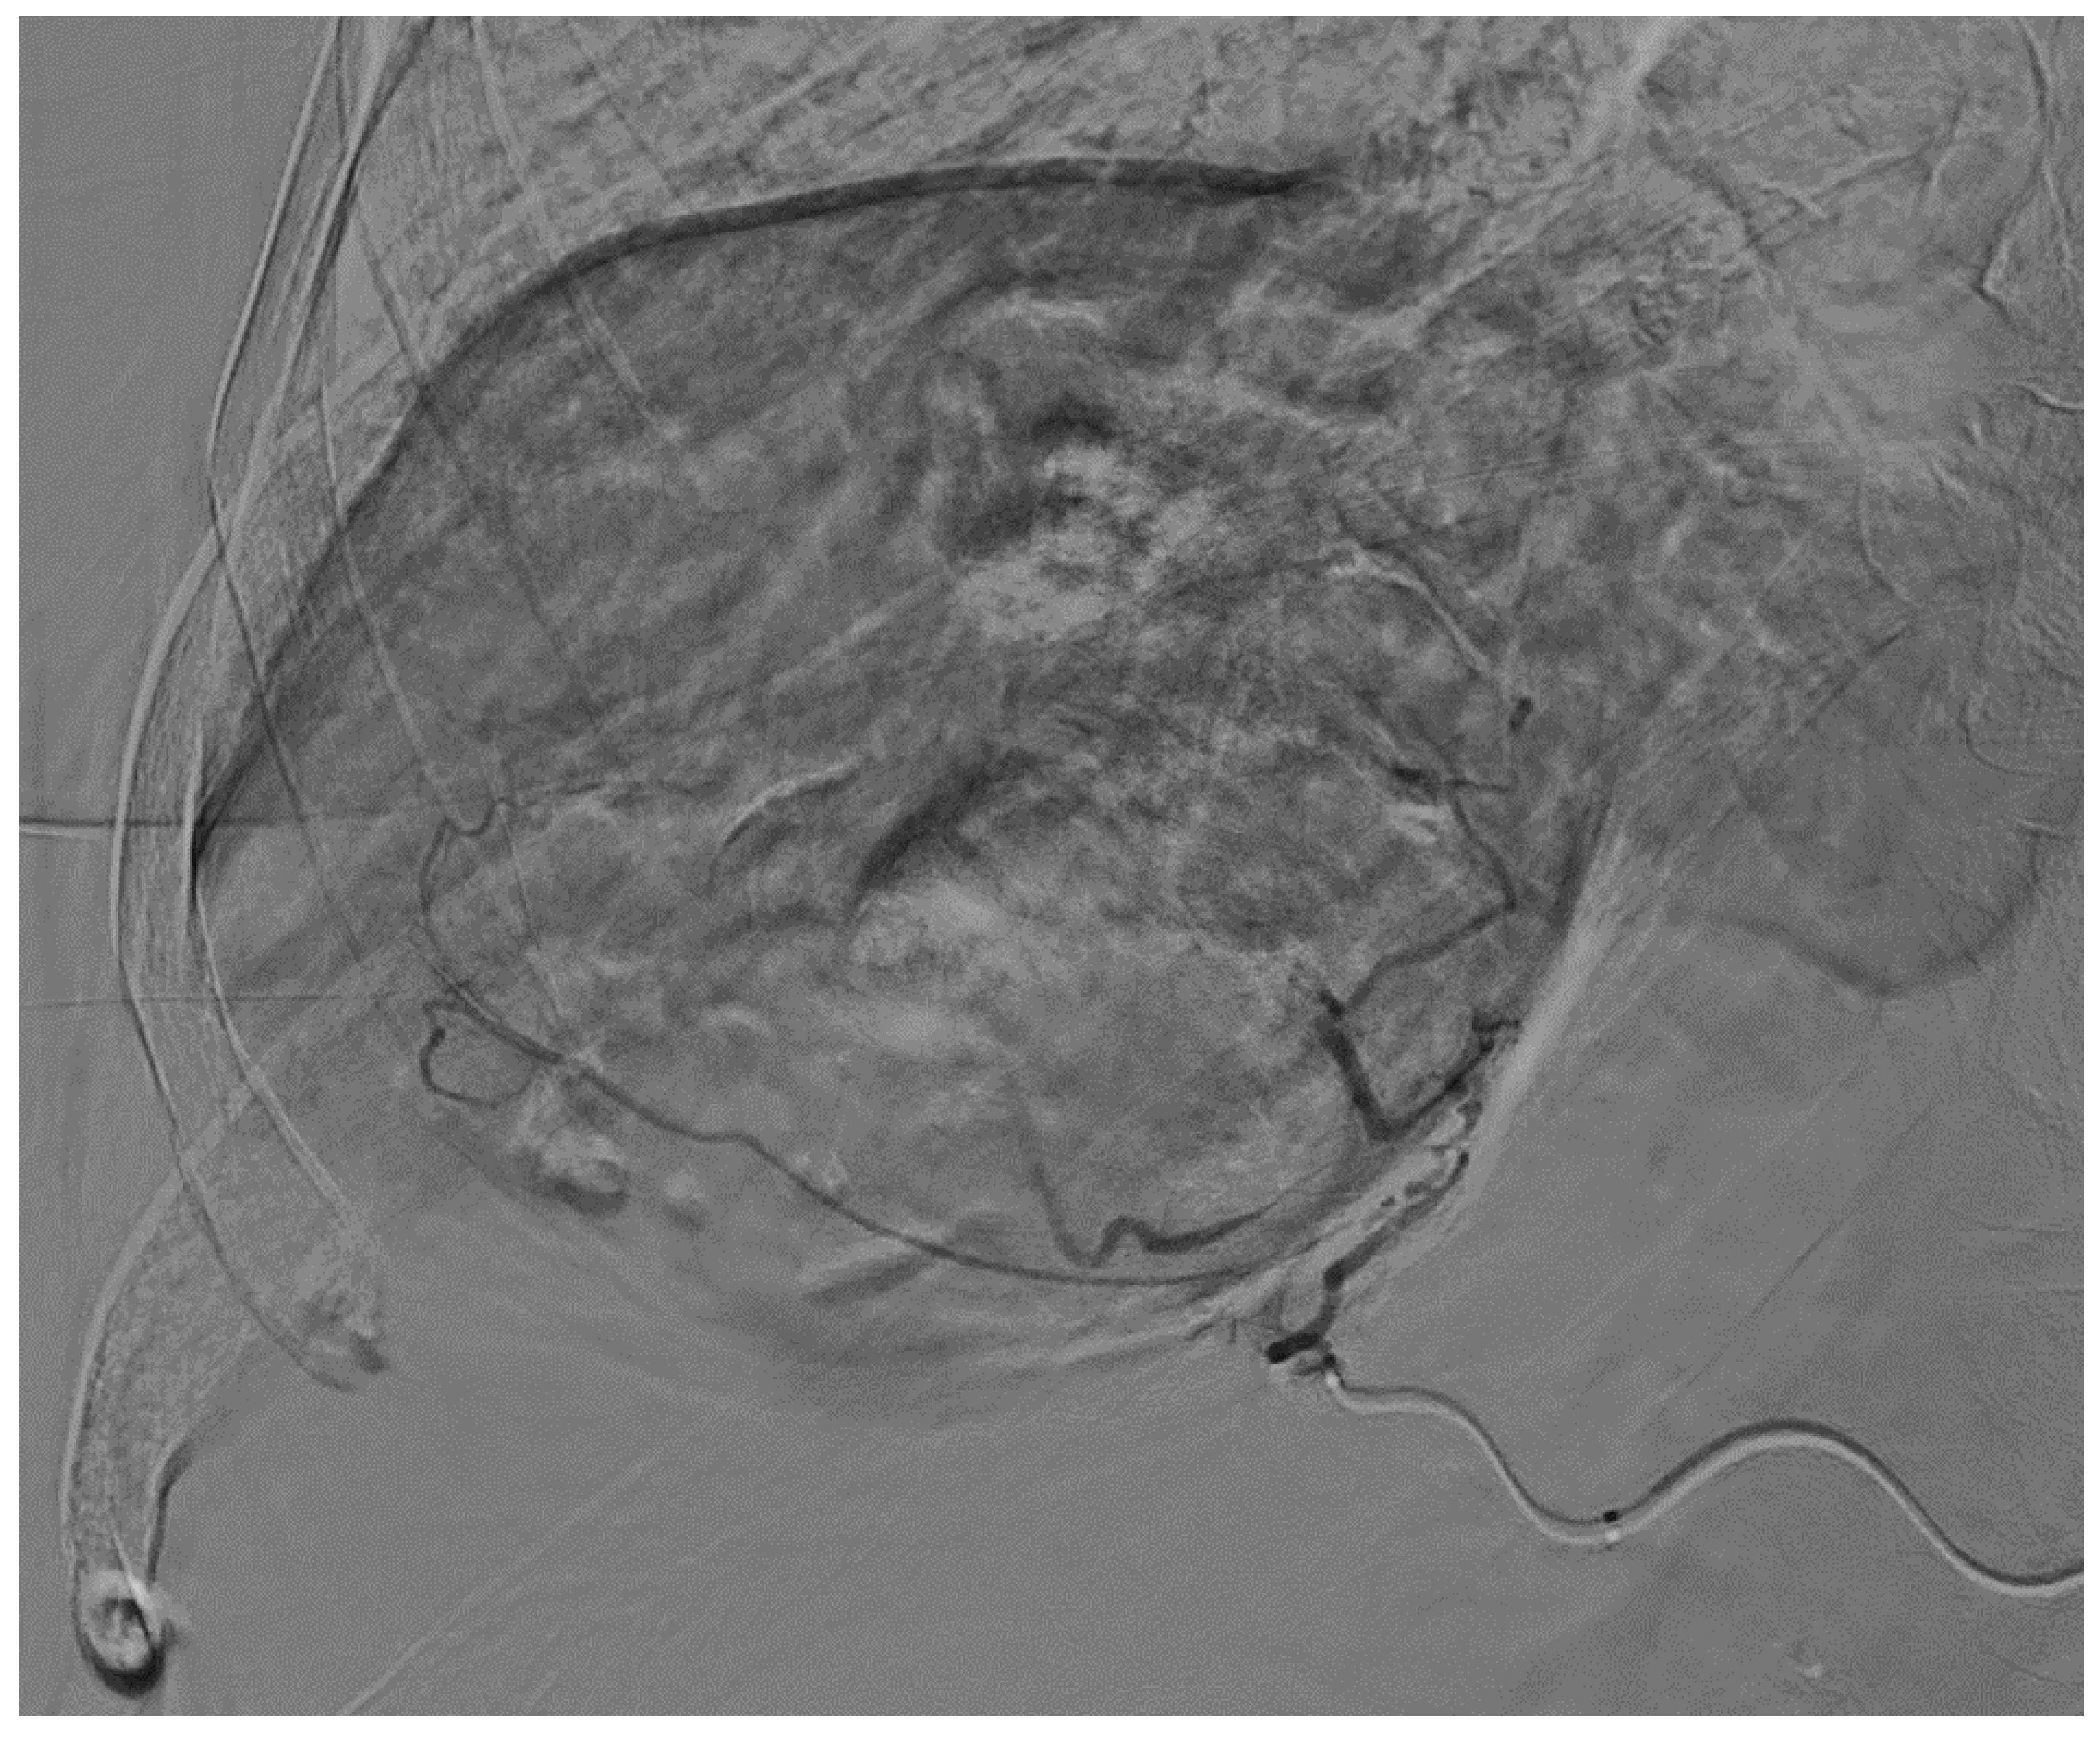

2. Case Report